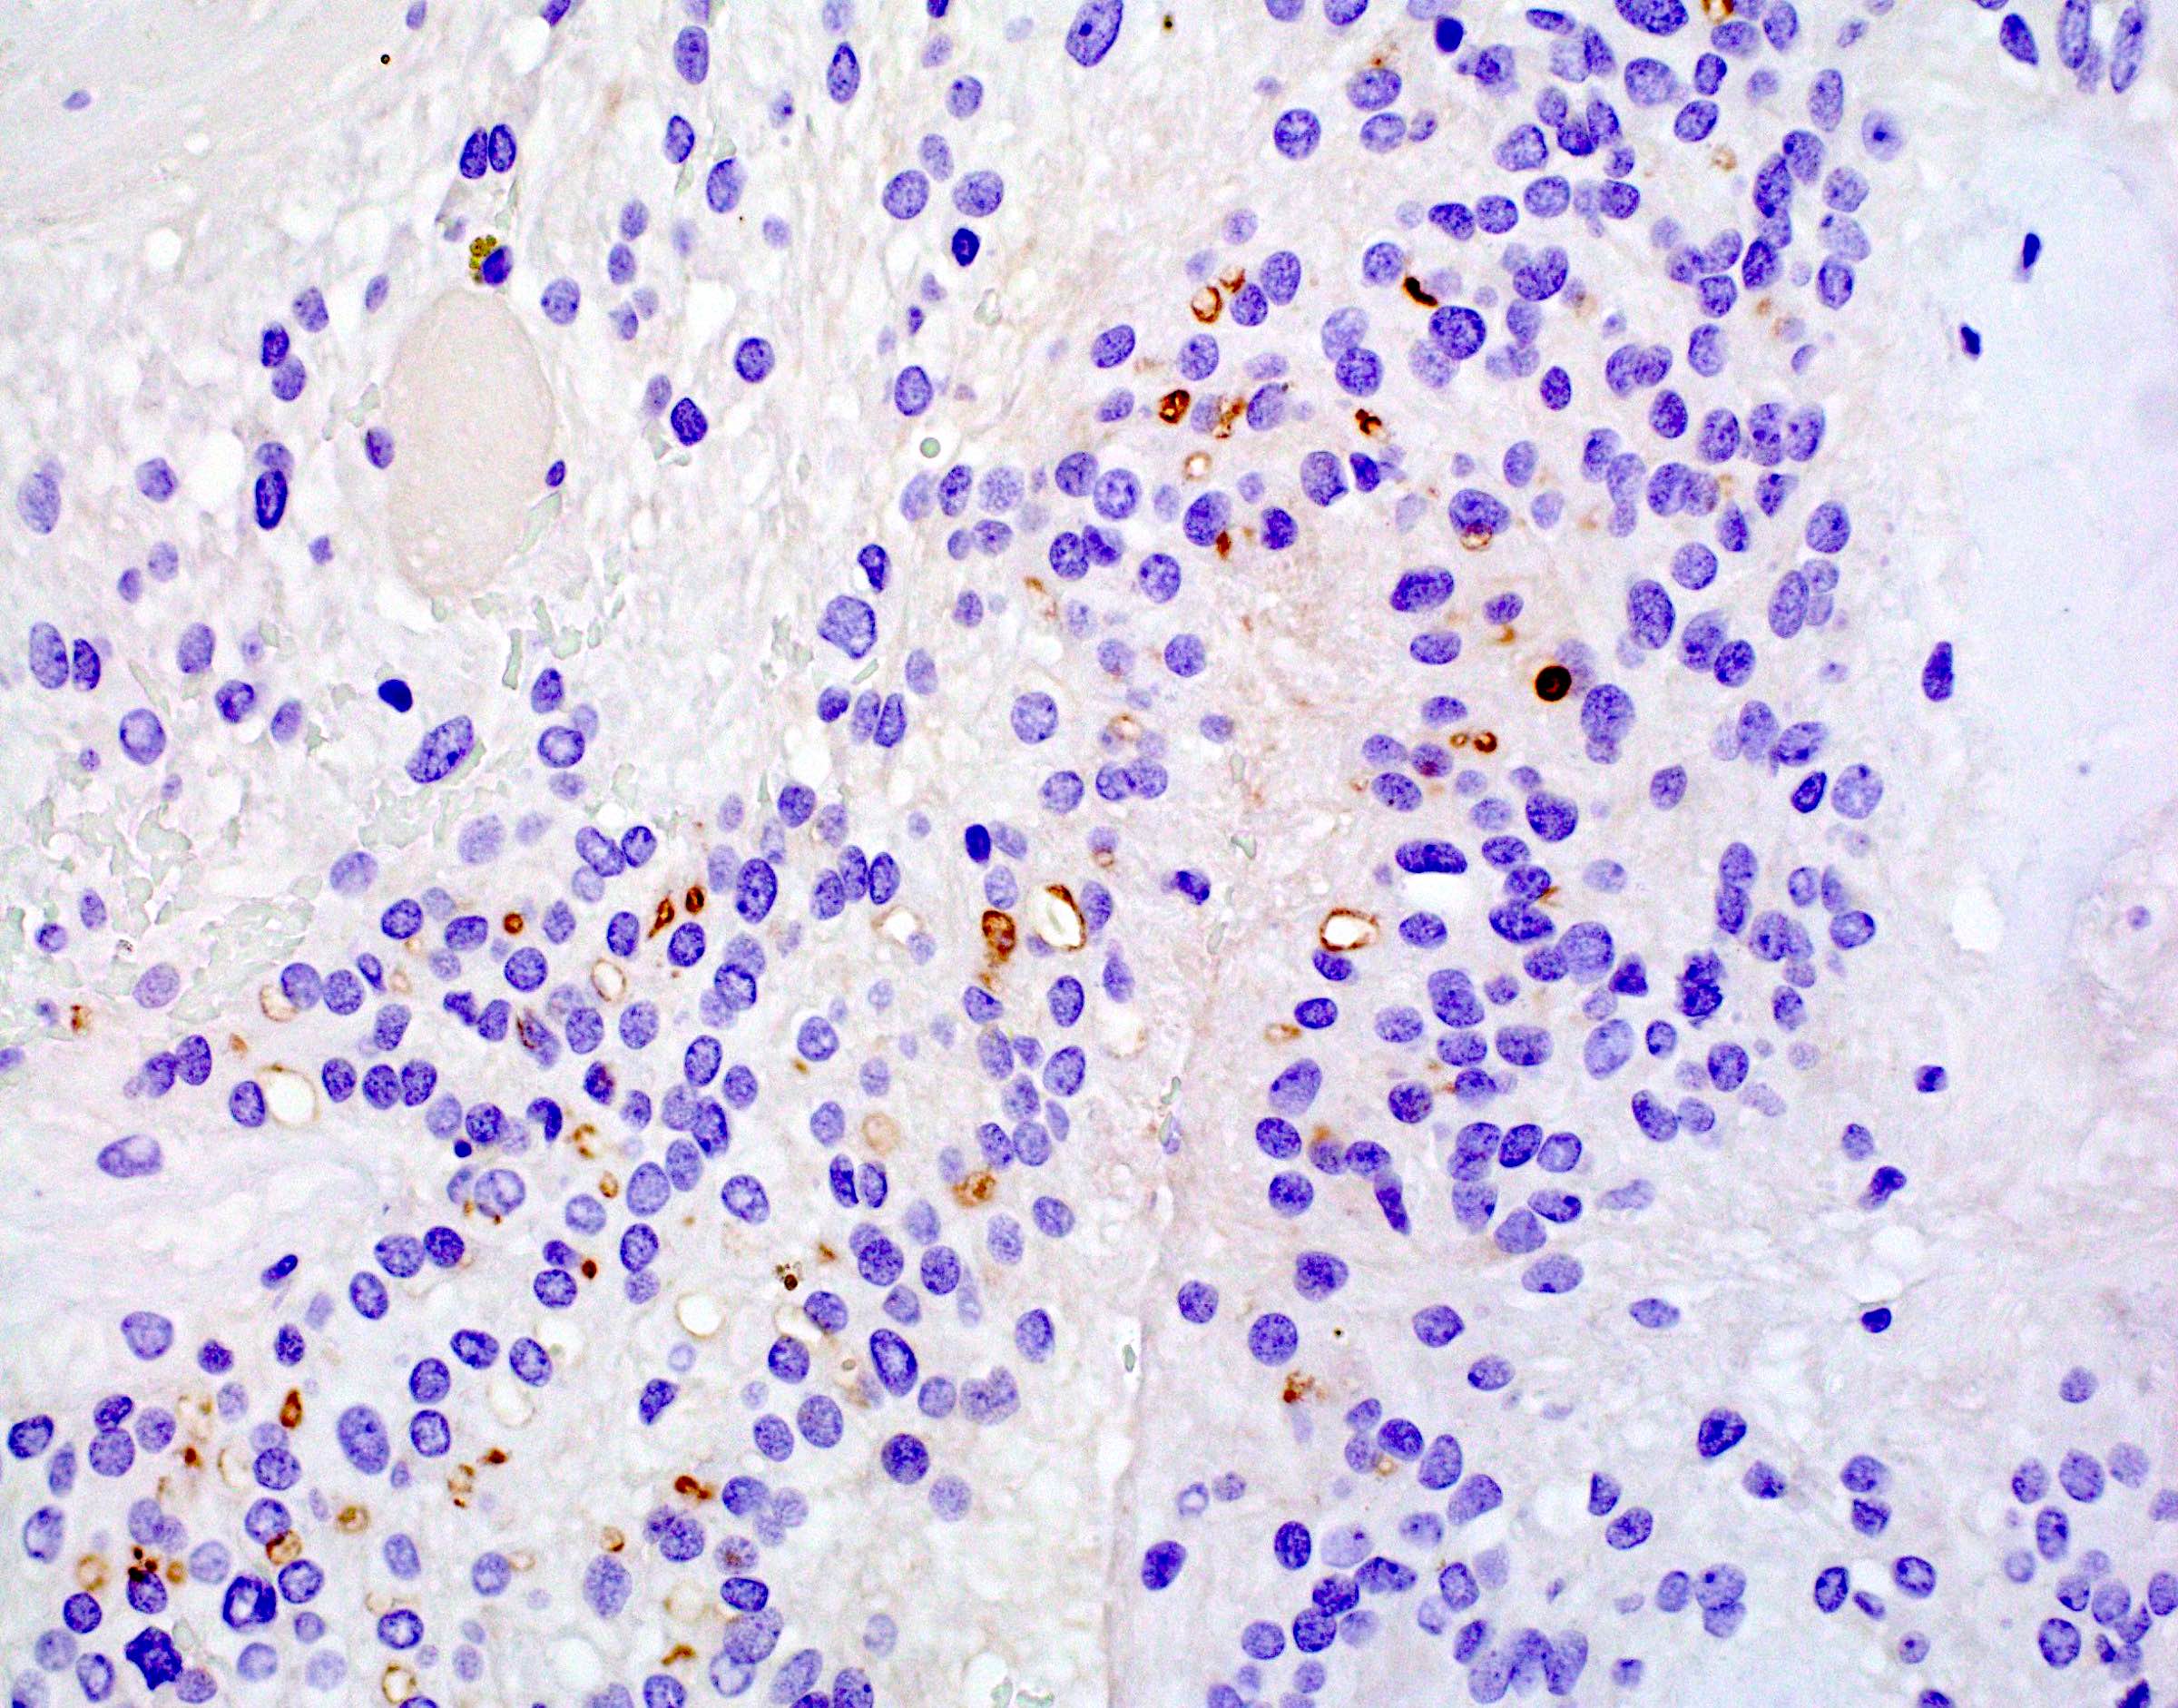

Microscopic (histologic) images

Positive stains

- Perinuclear dot-like pattern of EMA and D2-40 staining

- In posterior fossa ependymomas, decreased expression of H3K27me3 is seen in posterior fossa group A, which has a worse prognosis (Acta Neuropathol 2017;134:705)